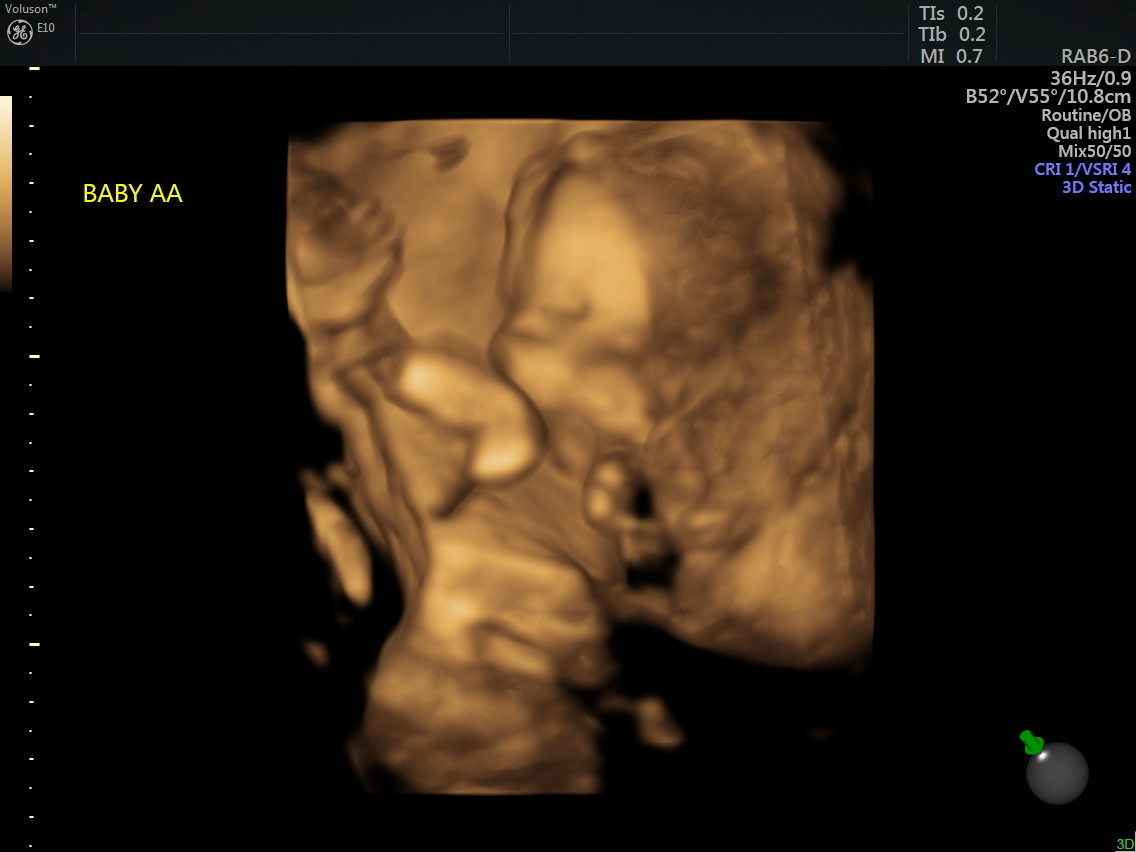

Bowen had been part of a social media group for those seeking to adopt out embryos. She said it was there that one post caught her eye. Both embryos had preimplantation genetic screening, or PGS. It had a one percent chance of successful implantation. Bowen and her husband chose to implant two of this woman’s embryos.

“I prayed they would both survive and that we would have fraternal twins,” she said.

The first trimester went very well, she said. However, at 15 weeks, Bowen’s water broke. “They told us Baby A lost his entire amniotic sac and his survival likelihood was very low.”

Baby B, she was told, had a probable survival rate of 30 percent. The doctors brought up the idea of selective abortion for Baby A and sent Bowen home to wait.

At 22 weeks Bowen began to lose more fluid. She was hospitalized and the babies were delivered at 24 weeks via emergency C-section this past January 2023.

Baby A, named Jeremiah, was born with a prolapsed umbilical cord. Before his birth, doctors were not certain he would have lungs. However, the baby boy was born with both lungs in place. He was intubated and placed in an isolette.

Jeremiah was born weighing one pound, six ounces. Twin Jonathan weighed one pound, 13 ounces. Jonathan was able to come home to the Bowen household in June. Jeremiah’s journey has been the most difficult.